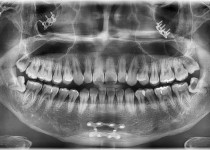

만 52세 전악 상악, 하악 전체 임플란트…

만 56세 상 하악 임플란트 증례